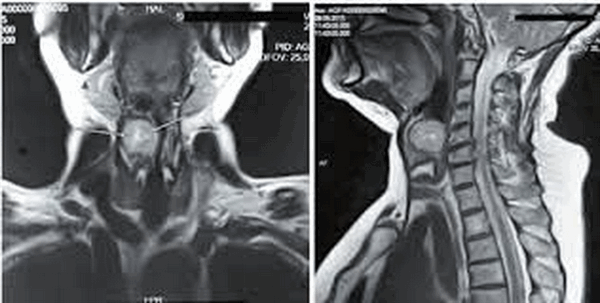

На фото МР-снимок органов лица, шеи и соответствующего отдела позвоночника

МР-снимок глотки и гортани

Киста шеи (щитоязычного протока) представлена на двух МР-снимках в разных режимах, имеет гиперинтенсивное содержимое на Т2 ВИ, четкий контур

Объемное образование в области гортани (стрелки): проекция спереди и сбоку